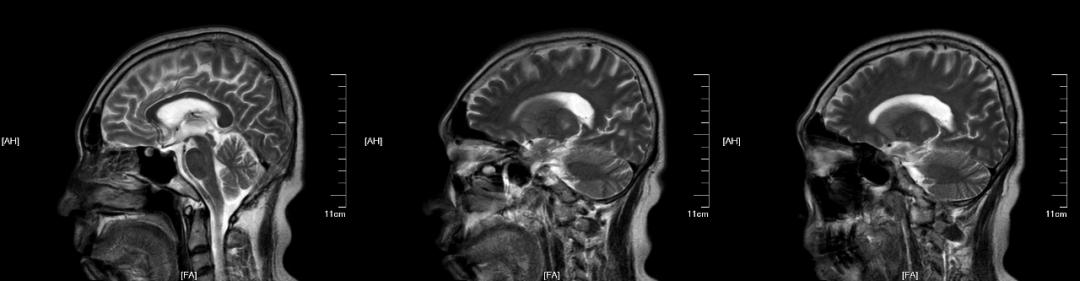

男,50 岁,患者 7 年前发现丙肝病原学阳性,未系统治疗,4 年前于当地医院诊断为肝炎后肝硬化 丙型 失代偿期,后规律应用病毒灵等抗丙肝药物治疗,现丙肝 RNA 已降为阴性。2018 年 11 月因「消化道出血」入我院,治疗期间明确诊断原发性肝癌,未规律治疗。25 天前患者进食烧烤后再次出现间断性呕血、便血,行胃镜套扎治疗,后病情好转后出院。患者 15 天前无明显诱因出现言语笨拙、流涎伴行走缓慢,具体表现为行走时脚尖着力,不需搀扶。

临床诊断:桥脑和桥外渗透性脱髓鞘疾病

桥脑分为前方的基底部和后方被盖,大部分患者病灶位于基底部,严重者可见被盖受累。病理变化往往与影像学表现相对应,最初病灶多位于中脑的中线附近,像「灌木丛一样」蔓延到周围的基底部,病灶可能延伸到中脑,但很少延伸至延髓。

(2)CPM,病灶多位于桥脑基底部而桥脑腹侧不受累,病灶形状多种多样,可为条片状(位于中脑基底部中线,如本例)、斑片状、圆形或卵圆状、「三叉戟」或「猪鼻」样,T1WI 呈低信号,T2WI 及 FLAIR 呈高信号,病灶边界清晰,部分患者出现 DWI 高信号,有利于疾病的早期发现,出现强化提示血脑屏障破坏。